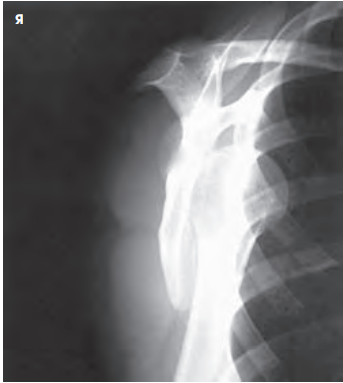

안녕하세요, 오늘은 어깨(shoulder) 촬영방법 중 하나인 shoulder Lateral oblique(Scapula Y view) 촬영법에 대해서 설명하겠습니다. 견갑골이 알파벳Y자로 보여 Y view라는 이름이 지어졌습니다. 이 촬영법은 어깨 dislocation(탈구)가 의심되는 환자 평가에 유용합니다.

영상평가

- body of scapula와 rib이 겹쳐지지 않게 한다.

- Coracoid process(오훼돌기)가 포함되어야 한다.

- 견갑골은 Y자 형상을 하여야 한다.

- 전방탈구의 경우 상완골두가 coracoid process아래에 위치한다

- 후방탈구의 경우 상완골두가 acromioclavicular process 아래에 위치한다